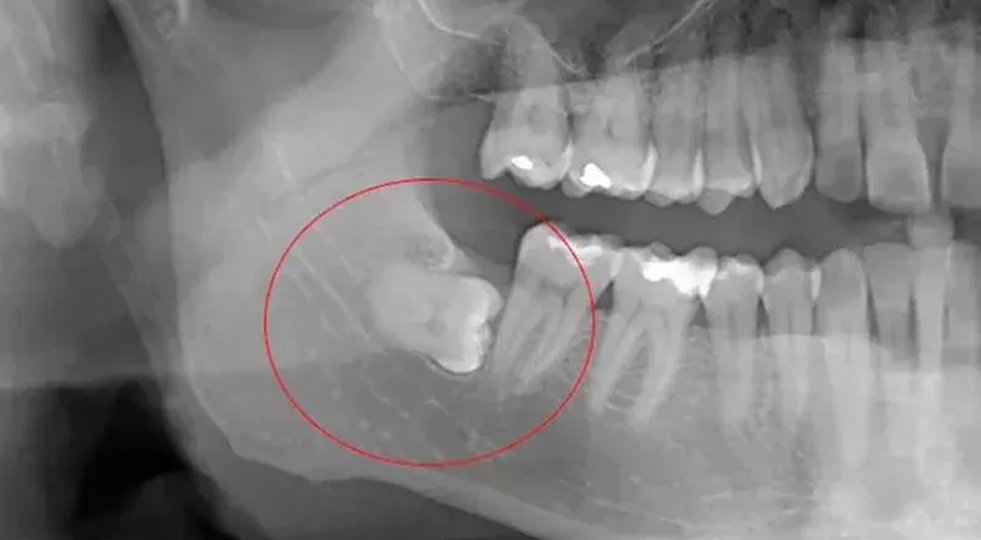

В государственную стоматологическую поликлинику центра одного из северных регионов РФ обратилась 33-летняя женщина, у которой после обследования был диагностирован непрорезавшийся (вследствие врождённого атипичного расположения в зубной лунке нижней челюсти) зуб мудрости с хроническим воспалением окружающих мягких тканей. Непрорезавшийся зуб мудрости в нижней челюсти (пример рентгенограммы). Лечение данной патологии заключается в хирургическом удалении зуба после резекции (раскрытия) костной лунки челюсти и предварительного дробления его бормашиной, что и было произведено больной. В раннем послеоперационном периоде лечащий врач стоматолог-хирург, не проведя обязательное контрольное рентгенисследование, обрабатывал операционное поле антисептиками и назначал медикаментозное лечение. Через неделю во время жевания пищи пациентка почувствовала и услышала треск в месте операции на нижней челюсти. При посещении пациентки поликлиники лечащий врач провёл рентгенисследование, но не только не оп